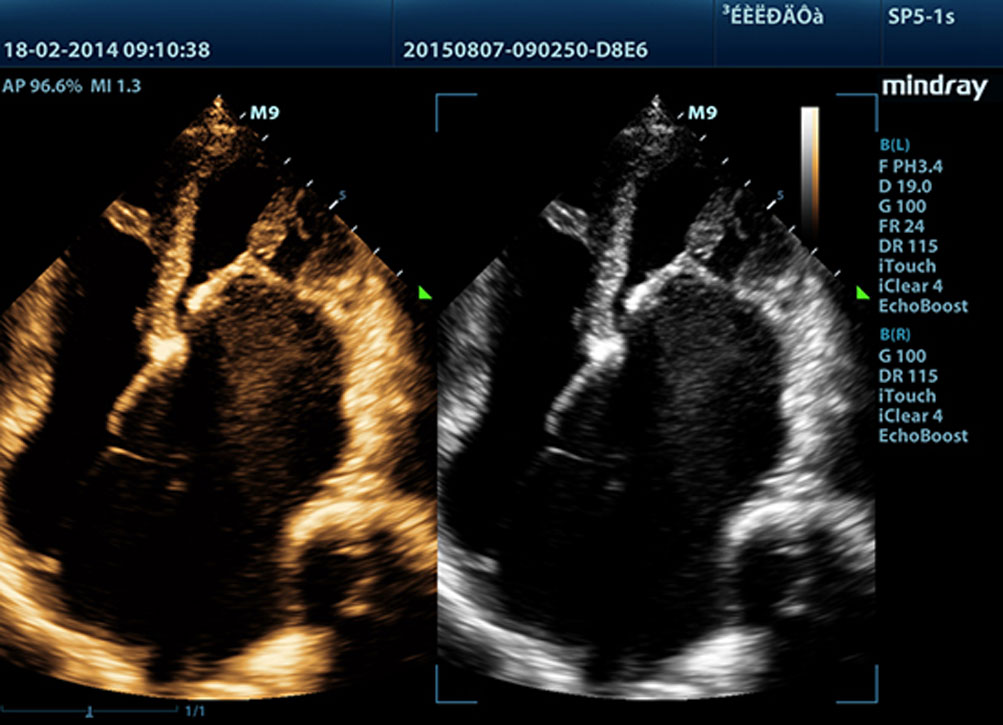

Echo Boost?

La tecnologĂa Ășnica de procesamiento de se?ales adaptativa de Mindray con detecciĂłn inteligente por eco ha sido dise?ada para utilizar la informaciĂłn nativa se?al-ruido con el fin de mejorar las se?ales de eco dĂ©biles suprimiendo al mismo tiempo el ruido y el desorden circundantes, proporcionando asĂ un brillo de imagen mĂĄs equilibrado y una visualizaciĂłn mejorada de las capas del miocardio.

LVO con ecocardiografĂa de estrĂ©s

Las capacidades superiores del M9 permiten la opacificaciĂłn LV durante el estrĂ©s, lo que mejora la discriminaciĂłn entre tejidos miocardiacos y coĂĄgulos de sangre y proporciona una mejor visualizaciĂłn de la superficie endocardiaca. La funciĂłn de ecocardiografĂa de estrĂ©s del M9 incluye un paquete completo para ecocardiograma de estrĂ©s farmacolĂłgico y de ejercicio. El paquete estĂĄ soportado por un sistema de informe flexible que puede ser optimizado para sus necesidades individuales.